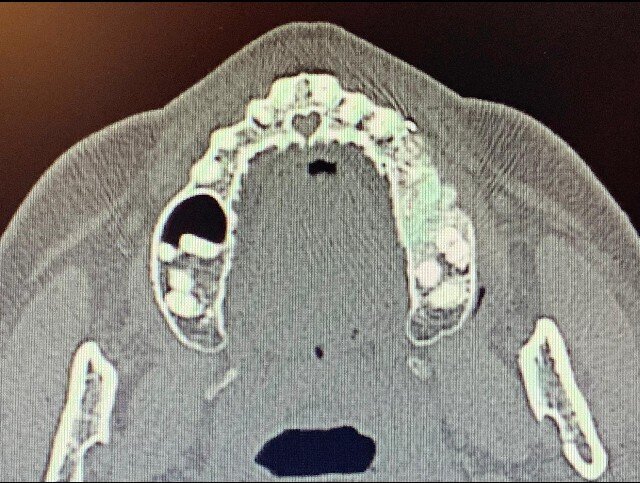

In seguito all’intervento di rialzo di seno mascellare con contestuale GBR è stata eseguita la radiografia ortopanoramica che mostra il corretto riempimento dell’area atrofica del seno mascellare con granuli cortico-spongiosi di osso di origine bovina. Al controllo dopo tre settimane i tessuti molli dell’area trattata risultano perfettamente guariti. La TC Dentalscan effettuata dopo 6 mesi per il controllo della zona rigenerata evidenzia la perfetta guarigione della zona con aumento dello spessore osseo di 5 mm e dell’altezza ossea di 11 mm.